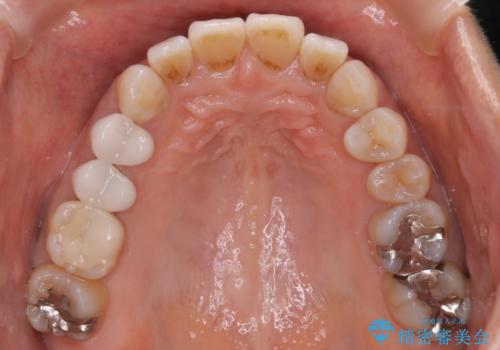

【インビザライン】下前歯だけを治したい

- 下前歯のがたつきにより唇を巻き込んでかんでしまい痛いため矯正をしたいという主訴で来院されました。今回は下顎前歯のみという強い希望があり、下顎のみのインビザライン矯正をしました。

叢生を改善するためのスペースはIPRと拡大を行いました。治療後は唇を巻き込んでしまう主訴が改善し、ご満足していただけました。